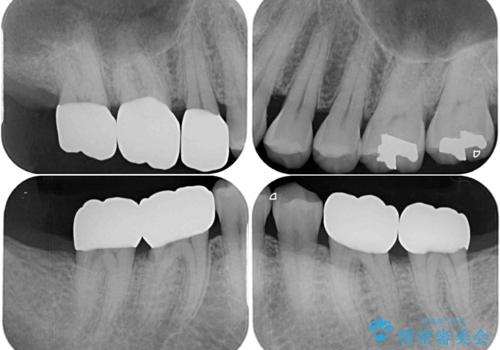

奥歯の歯間部の歯肉が炎症で赤黒くなっており、歯周ポケットを検査したところ、6-8mm(正常では3mm以下)であり、外科処置が適用となる状態でした。

まずは仮歯に置き換え、歯周ポケットを除去するための外科処置(歯肉弁根尖側移動術)を行い、治癒を待ってセラミッククラウンにて補綴治療を行うこととしました。